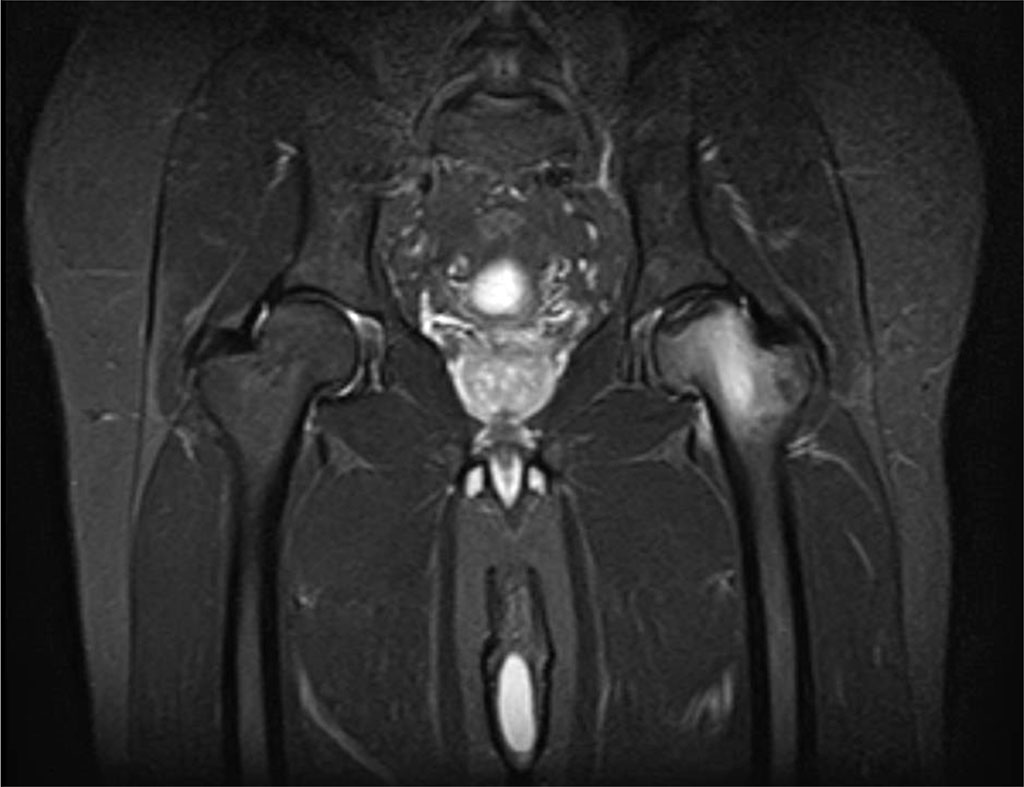

The first patient was a 53-year-old man. It was found that he had hip and leg pain for one week, which did not go away despite the drugs he was using, and was now unable to move. He had undergone cervical disc surgery before, and his VAS score was 90 mm. Lumbar MR images showed protrusion. Due to severe foot pain, a hip MRI was requested as a further examination. In his history, it was determined that he had walked 20 kilometers without stopping during a trip abroad one day before the onset of pain, and he started the next day with this pain. In his neurological examination, he had no motor deficit and could not stand on his left foot due to pain. There was no lumbar or hip tenderness. Since the patient's lumbar MRI images are not compatible with the patient's clinical condition; the patient was re-examined with an MRI of the hip as an additional examination. The MRI of the hips revealed that the right hip had stage 2 avascular necrosis and the left hip had stage 3 avascular necrosis. (Figure 1).

Figure 1. Findings in a 53-year-old man with stage 3 avascular necrosis of the left hip.